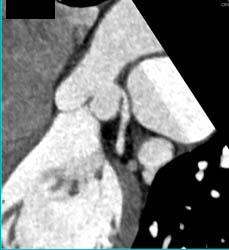

Diagnosis

RCA Branching